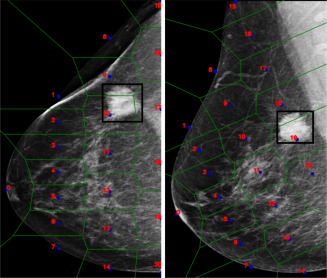

图1.Wu et al. (2020)提出的NYU模型的示意图。骨干参数在相同视图(CC和MLO)的图像之间共享,如不同颜色所示。损失根据softmax输出计算,并在推理时对CC和MLO视图的预测进行平均。

图2.同一乳房在两种投射下的伪特征点及其相应镶嵌的表示。